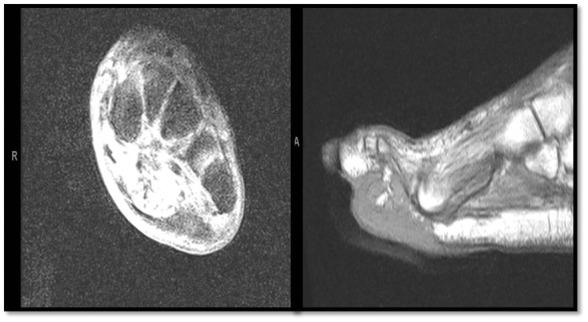

Limb salvage of the foot with Lisfranc amputation following squamous cell carcinoma.

The indolent character of squamous cell carcinoma of the foot can be misleading and might result in unwarranted excisions or delayed treatment.